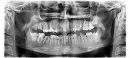

Врач по снимку сказал устанавливать коронки. Он предложил коронки не только на нижние, но и на верхние зубы, аргументируя тем, что они гниют изнутри. Причем коронки на вкладках. Все верхние с правой и левой стороны с пятого по седьмой. Но верхние меня не беспокоят.

Несколько зубов необходимо удалить, в том числе и все восьмые зубы и 46 зуб. В идеале мостовидные протезы ни с одной, ни с другой стороны - неактуальны. Запишитесь на очный прием и вам расскажут подробно правильные методы лечения.